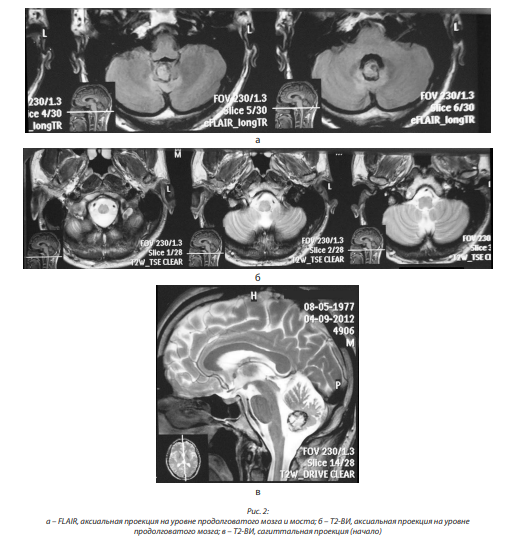

Удалил три зуба на верхней челюсти, принимал карбамазепин по три таблетки в день, однако эффекта не отмечал. Летом 2016 г. консультирован в 1-м нейрохирургическом отделении ГМПБ № 2. При МРТ головного мозга и ствола выявлен вазоневральный конфликт с правым тройничным нервом. В августе 2016 г. выполнена двухэтапная операция декомпрессии правого тройничного нерва с выраженным положительным эффектом (боль исчезла и не беспокоит). Начиная с марта-апреля 2017 г. заметил неустойчивость при ходьбе, которая постепенно прогрессирует, особенно с конца мая; отметил постепенное увеличение площади онемения участков левой половины тела, при этом нога онемела полностью (в течение месяца). При ходьбе стал пользоваться палочкой. Повторно поступил в нейрохирургическое отделение для обследования. При МРТ головного мозга от 21.06.2017 выявлены очаговые изменения в области олив продолговатого мозга, характерные для ГДО (рис. 6, а, б).